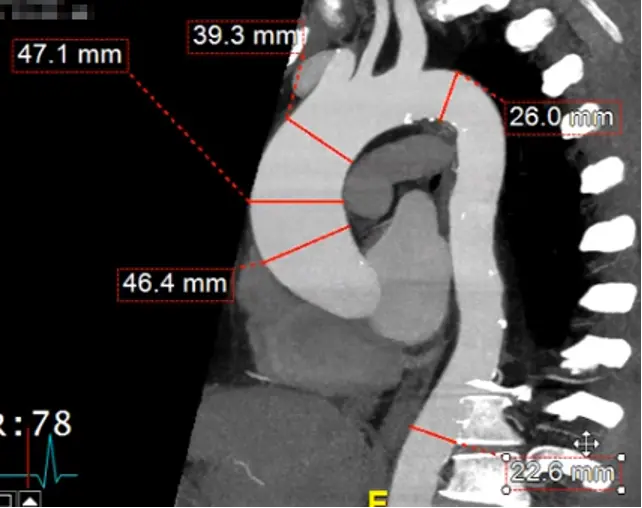

Measure aorta using âcandy caneâ view

- Rotate your cross hairs so you are cutting through both the ascending and descending thoracic aorta.

- Last step is to click the

MPRbutton at the top right and change it toMIP - Hit

Ctrl, hit the button down and drag sideways, you can increase/decrease the slab thickness. For example, this may allow you to capture the entire thickness of the aorta in different planes by manipulating the slab thickness. - Hit

Dto make measurements at different levels of the aorta. Provides a sanity check to make sure you didnât miss a larger/wider part of the aorta. - Right-click and select âCaptureâ to store this image with your measurements.